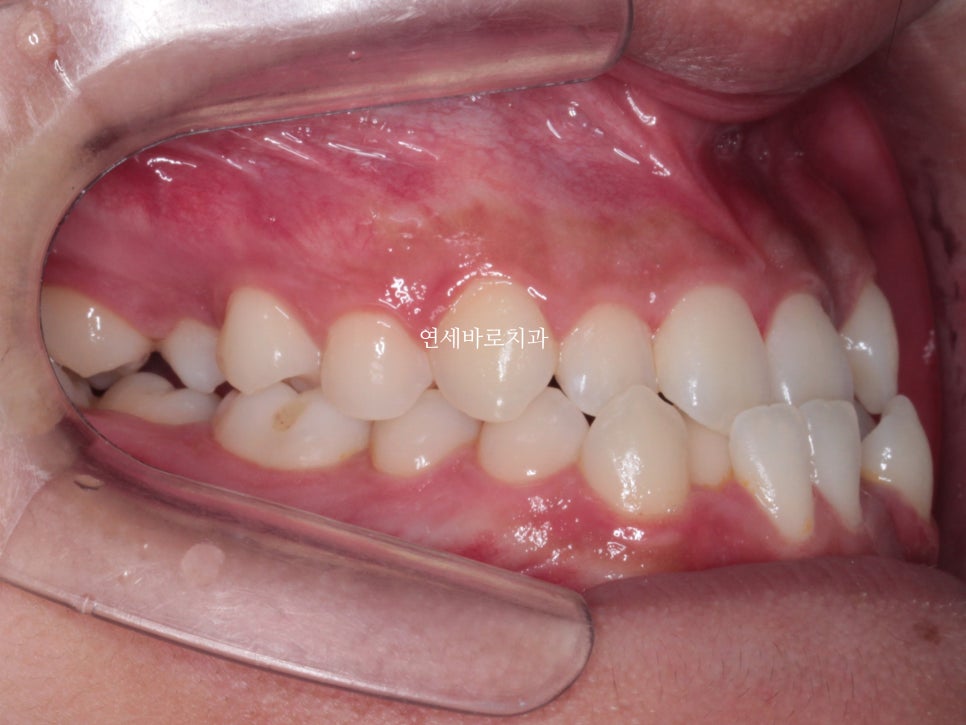

최근에 오셨을때 모습입니다.

아쉽게도 처음 끝날때와는 약간은 다른 중심선을 관찰하였습니다.

하지만 좌우 교합은 긴밀하게 유지되고 있었고 안모의 변화 등 다른 부작용은 관찰되지 않았습니다.